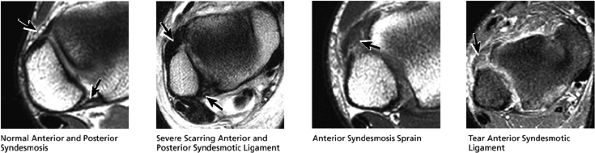

FIGURE 5.43 High Ankle Ligaments.